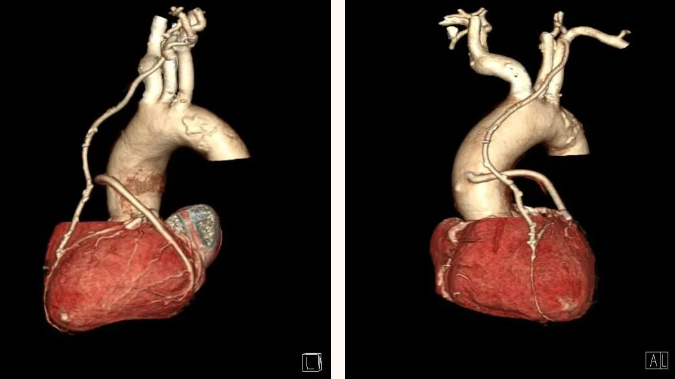

CT 血管造影(CTA),即 CT 血管成像,是一种利用计算机三维重建方法合成的非创伤性血管成像技术,可以在没有创伤的情况下,很好地了解身体中血管的情况。具有时间短、无创、特异性和敏感性高,时间和空间分辨率高等特点,能全方位显示出血管病灶,对于经其他检查已经明确患有血管疾病,需进一步了解病情严重程度具有重要的意义。

通过 CT 血管成像,可显示动脉病变,如血管闭塞、动脉瘤及夹层动脉瘤、血管畸形、血管损伤、心脏冠状动脉病变等。可进行冠心病 CT 筛查,冠心病术前、术后评估,脑卒中一站式检查,灌注成像等。

CTA 检查在大血管、外周血管疾病、心脏冠状动脉相关疾病、中枢神经系统疾病以及肿瘤疾病的诊断中发挥着重要作用。